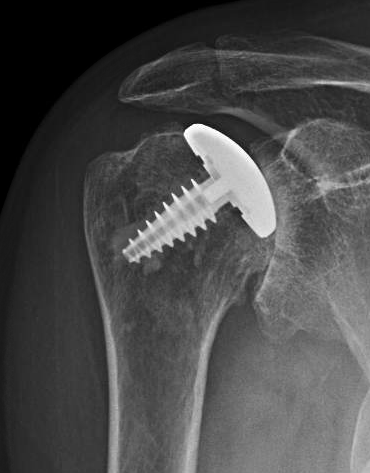

This was revised to a traditional hemiarthroplasty, which replaced the arthritic humeral joint surface with a smooth prosthetic humeral head secured by an impaction grafted stem in the medullary canal. No glenoid arthroplasty was required. The postoperative x-rays are shown below.